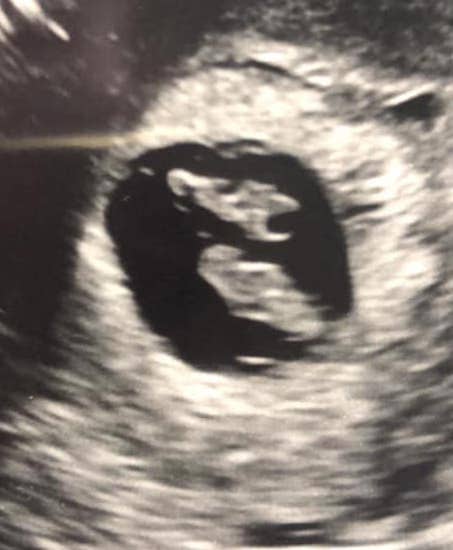

Early Twin Ultrasound at 7 Weeks

The earliest your doctor would likely order an ultrasound confirming twins would be 4 weeks pregnant. But unless you are going through fertility treatments, doing an ultrasound before 6 weeks isn’t very common, with the exception of complications. Women who are going through fertility treatments or have early complications may be able to have an early twin ultrasound at 4 or 5 weeks pregnant and find out they are pregnant with twins.

At four to five weeks after a pregnant woman’s last period the ultrasound commonly shows a small collection of fluid within the lining of the uterus that represents the early development of the gestational sac. At about five and a half weeks after a pregnant woman’s last period the ultrasound typically shows a gestational sac and within it we can see a 3-5 mm bubble-like structure, which is the yolk sac. At approximately six weeks after a pregnant woman’s last period, we can see a small fetal pole, one of the first stages of growth for an embryo, which develops alongside the yolk sac.

Can You Tell at 7 Weeks if Its Twins?

Yes! You’d need to have an ultrasound at 7 weeks to confirm a twin pregnancy. Your twin belly at 7 weeks may not look like much of a belly at all, so getting in to your doctor for an ultrasound is key to find out if you’re really having twins.